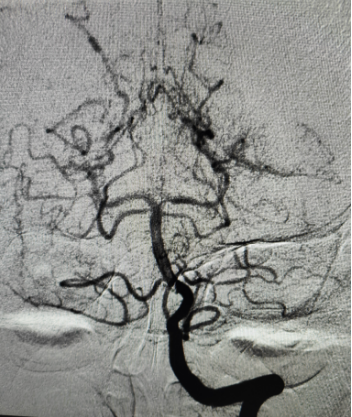

术中所见:

左侧大脑中动脉近端闭塞,新生血管形成呈烟雾状,由左侧大脑前动脉及大脑后动脉经脑膜支代偿。

右侧大脑后动脉重度狭窄。

结合造影表现,患者右侧大脑中动脉闭塞代偿较完全,左侧大脑后动脉重度狭窄,给予患者制定合适治疗方案,预防卒中再次发生。